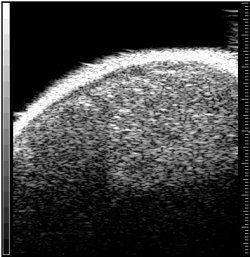

Above, ultrasound image of NHL xenograft done on a 20-MHz transducer at five hours after CHOP chemotherapy. The apoptotic areas correspond to the areas of high-intensity backscatter. Below, corresponding histology image with TUNEL stain. The areas that are stained brown correspond to the apoptotic areas. Images courtesy of Dr. Charles Cho.

For the study led by Cho, NHL tumors were placed in severe combined immunodeficiency disease (SCID) mice. These tumor-bearing animals were then treated with single doses of 8 Gy or with one to two cycles of cyclophosphamide, hydroxydaunomycin, vincristine, and prednisone (CHOP) chemotherapy.

The animals were then imaged with 20-MHz spectroscopic ultrasound (VS40B, VisualSonics, Toronto). For the 26 mice that had chemotherapy, imaging was done several times, five to 72 hours after treatment. For the eight mice that had radiotherapy, sonography was performed once, six hours after treatment. Tumor sections were terminal transferase dUTP nick end labeling (TUNEL) stained to confirmed apoptotic cell death.

The authors found a time-dependent increase in backscatter following CHOP chemotherapy, they wrote in their results. The measured high-intensity (10-decibel increase) patch areas on ultrasound were 1.76 mm² at five hours, 0.27 mm² at 12 hours, 2.03 mm² at 24 hours, 2.93 mm² at 48 hours, and 0.12 mm² at 72 hours.

Based on spectroscopy results, the midband fits changes from -51 dBr to -44 dBr after chemotherapy. The spectral slope was invariant at 0.66 dBr/MHz pretreatment and -0.60 dBr/MHz at 48 hours post-treatment.

"Image analysis demonstrated a correlation between the size of high-intensity patches on high-frequency ultrasound and immunohistochemical TUNEL staining or apoptotic areas," the group wrote.